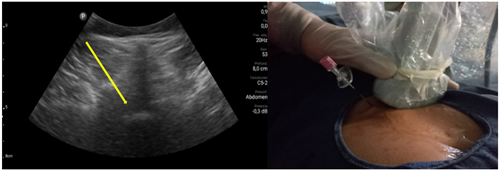

Los procedimientos fueron realizados en sala de operaciones, con vía venosa periférica y en posición decúbito ventral. Los mismos fueron realizados por el investigador principal (P. C.) con experiencia en la realización de procedimientos ecoguiados en la columna vertebral, utilizando la técnica paramediana en eje ecográfico corto. Se utilizó un ecógrafo portátil modelo Lumify marca Phillips, con transductor curvo de baja frecuencia. Fundas y gel ecográfico de la marca Pajunk® (Pajunk GmbH Medizintechnologie, Geisingen, Germany). En cada caso se identificó el espacio L4-L5 o L5-S1 mediante escaneo ecográfico de la columna lumbosacra en el plano transversal y longitudinal previo al inicio del procedimiento. Con la sonda ecográfica colocada en plano transversal o en eje corto, se realiza un habón anestésico 1 a 2 cm a un lado del transductor, correspondiente al lado del dolor radicular. La aguja de Tuohy ecogénica, 18 G (Tuohy Sono, 18G Pajunk® GmbH Medizintechnologie, Geisingen, Germany) de 9 o 12 cm según la contextura del paciente, se dirige en plano, en tiempo real, en sentido lateral a medial, entre la articulación facetaria por fuera y el ligamento interespinoso por dentro, hasta alcanzar el ligamento amarillo, en el espacio interlaminar elegido (Figura 1). El espacio epidural fue identificado mediante la pérdida de resistencia con suero fisiológico. Se registró la imagen doppler color durante la maniobra, como medida alternativa a la epidurografía con contraste (Figura 2). Posteriormente, 5 cc de contraste no iónico fue inyectado. Se consideró que fue alcanzado dicho espacio cuando el contraste se distribuye a lo largo del ligamento longitudinal posterior (Figura 2). 1 mg/kg de triamcinolona más 3 cc de lidocaína al 0,5 (hasta 10 cc de solución total) se inyectan en el espacio epidural.

Fig. 1. Escaneo ecográfico en eje corto o transversal del espacio L5-S1. La flecha amarilla muestra el punto de entrada de la aguja de Touhy en el abordaje paramedial y su trayecto. A la derecha se muestra la colocación de la aguja Sono Touhy en plano con el transductor curvo.